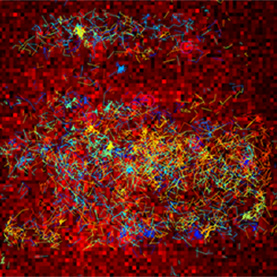

Pathogens are a major factor affecting the evolution of primates. We know very little about how historical pandemics have affected the genomes of different populations. This image results from research that examines how genetic variation and historical exposure to one of the most virulent pathogens known in human history, the plague, has affected immune system evolution and human health.

In the center of this image we see human white blood cells (labeled blue) confronted with bacteria. To protect the body from this invader, the cells capture the bacteria by throwing nets made from their own DNA. The cells are laid over tracks that evoke those seen in bubble chambers, another innovation used by researchers to see into the smallest spaces and understand movement and action on the smallest scales.